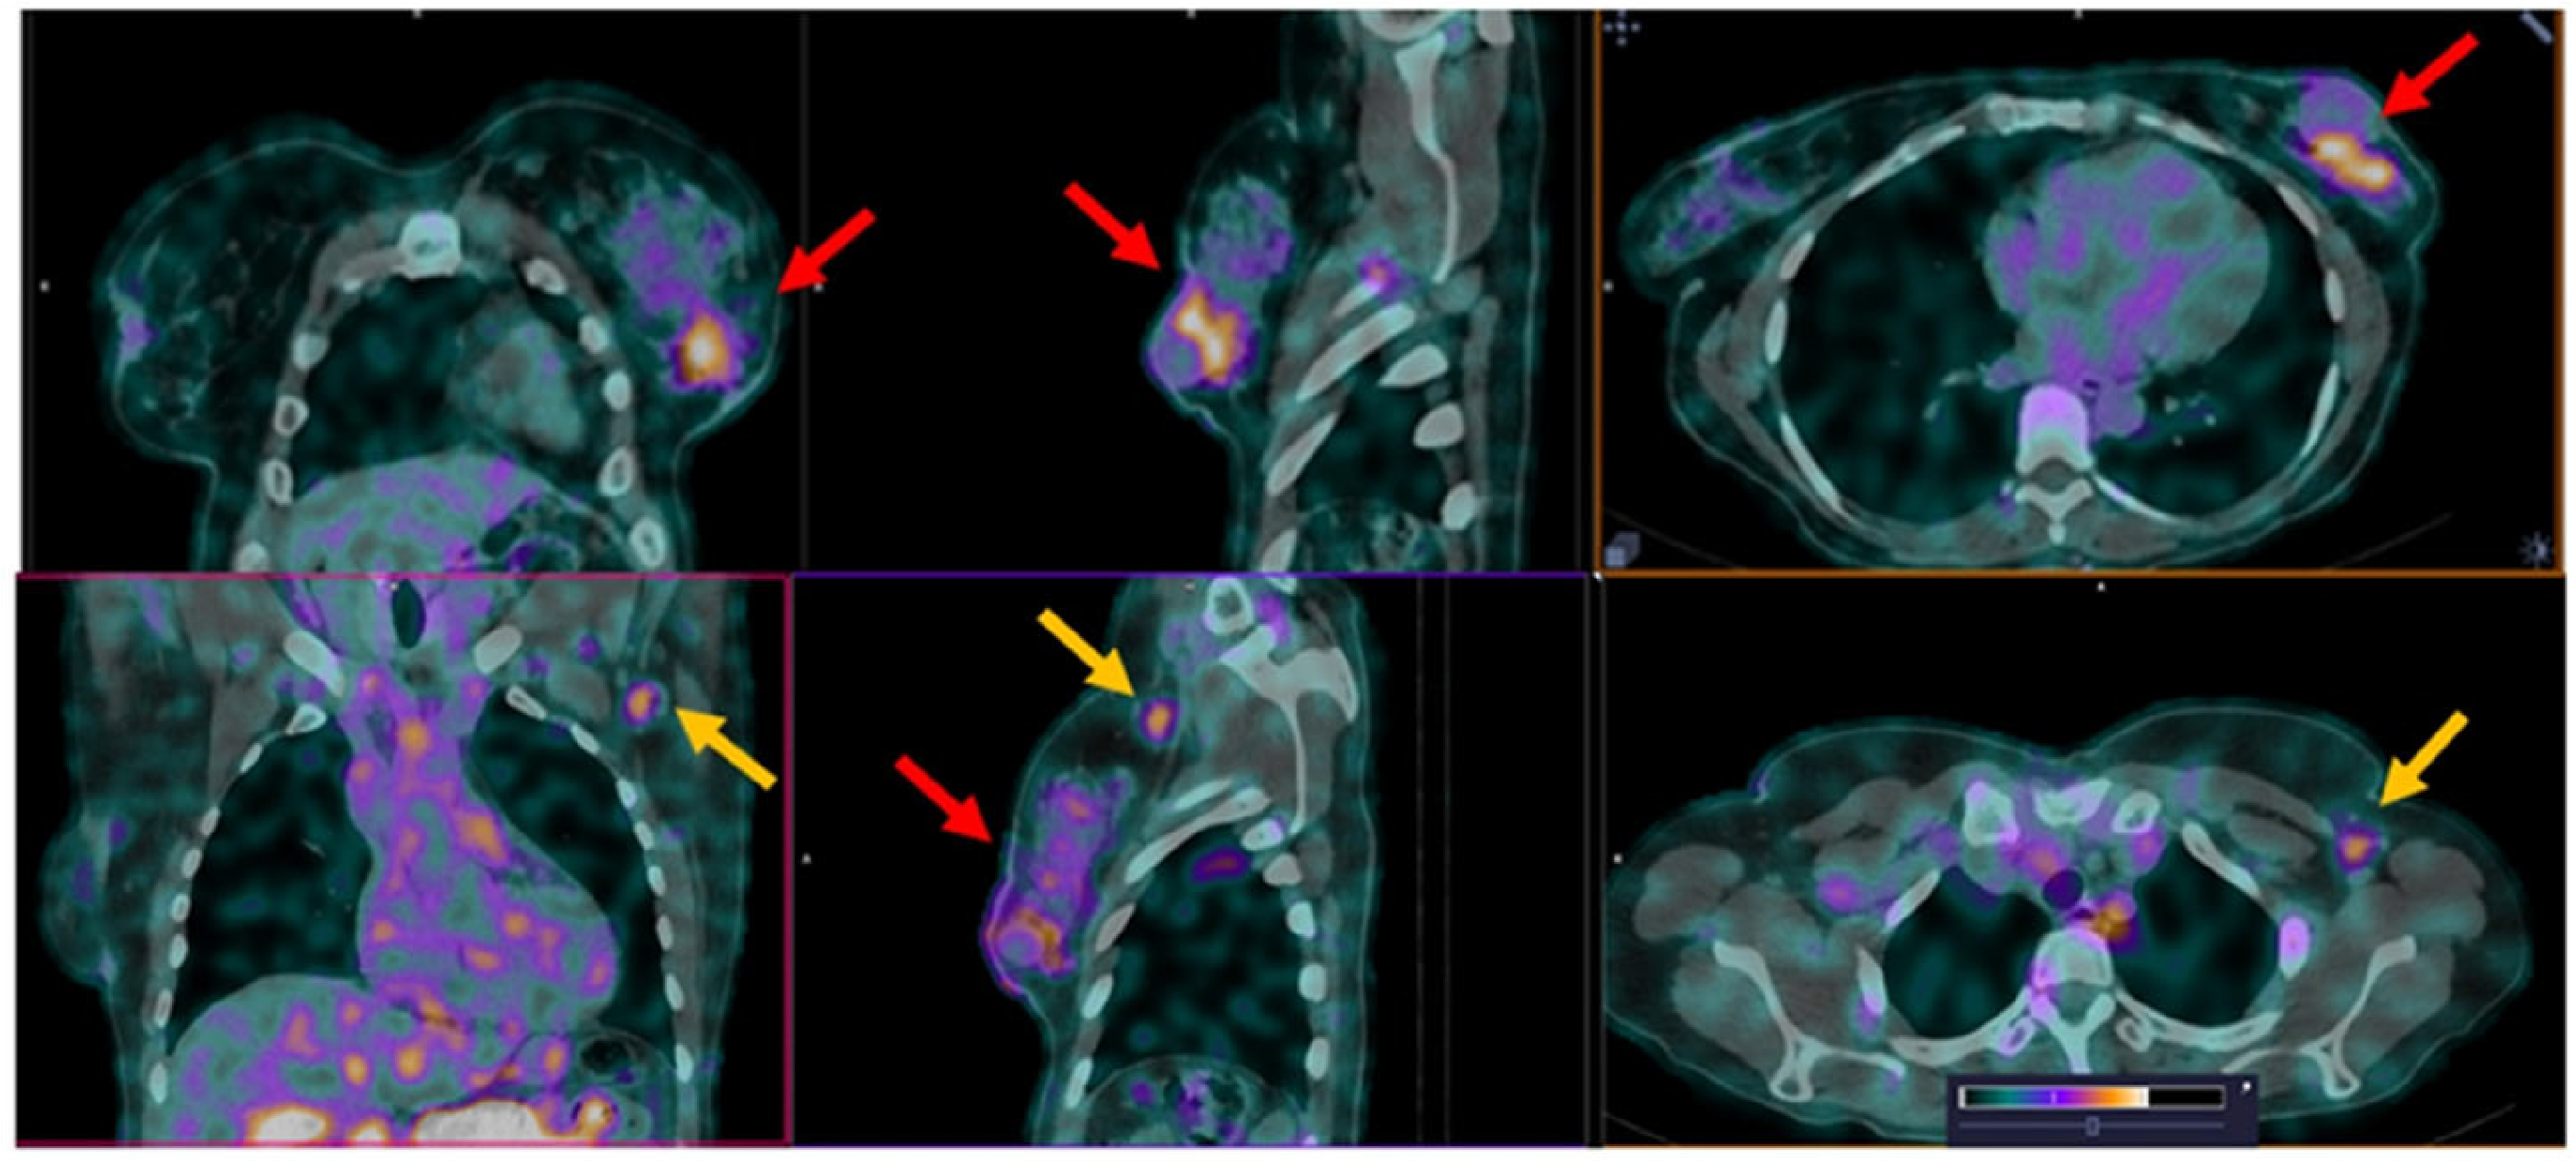

3. Results